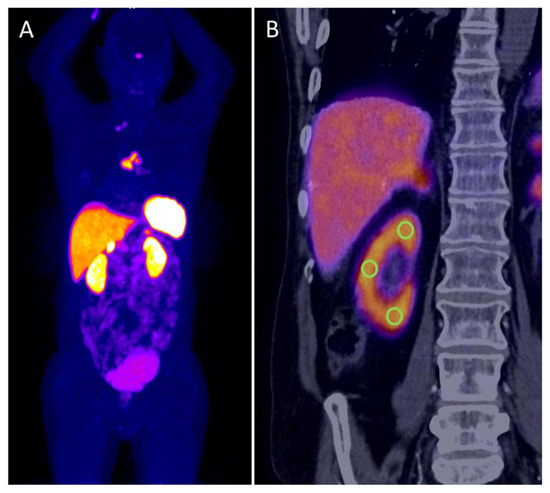

To avoid interobserver variability, only one examiner experienced in PET/CT diagnostics measured renal tracer uptake. Dedicated PET/CT evaluation was conducted without knowledge about kidney function. Standardized uptake values (SUV) were determined at the renal parenchyma, identified with anatomical CT information. Per kidney, the SUVmax was assessed, as well as the SUVmean of three defined volumes of interest (VOI) with a diameter of 1 cm at the upper and lower kidney pole, and the lateral aspect of the kidney (Figure 1). For comparison with the global kidney function, the mean value was then calculated from the SUVmax and the three SUVmean for both kidneys, respectively. Additionally, tracer concentraction in the urine was measured in both renal pelvis and the urinary bladder (SUVmax). For comparison, extrarenal organs were quantified. SUVmax of typical DOTATOC-positive organs, i.e., pituitary gland, thyroid, spleen and adrenal glands were acquired. Additionally, the SUVmean of surrogates of background compartments were measured in the blood (ascending aorta), muscle (gluteal musculature), liver (parenchyma) and bone (4th lumbar vertebral body). In all measurements, care was taken to ensure that no tumor manifestations were included in the VOI. The individual tumor burden was categorized visually as none, low (less than 5 tumor lesions) or high (5 or more tumor lesions).

Figure 1. Maximum intensity projection of 68Ga[Ga]-DOTATOC PET with high tracer uptake in intrathoracic tumor manifestations, kidneys and typical SSTR-expressing organs (A). PET/CT coronal view of right kidney is showing the uptake in renal cortex and the localization of the three defined VOIs for SUVmean measurements, which were averaged with measurements of the contralateral kidney (B).